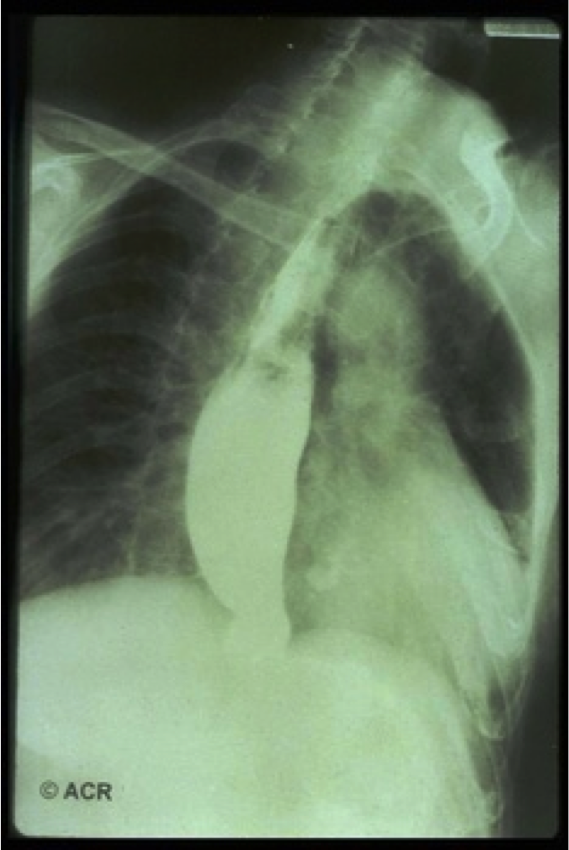

This is a pic of what? What disease is it associated with?

Barium swallow: indicates esophageal dysmotility.

Would be the E of CREST

Systemic Scleroderma, Limited type